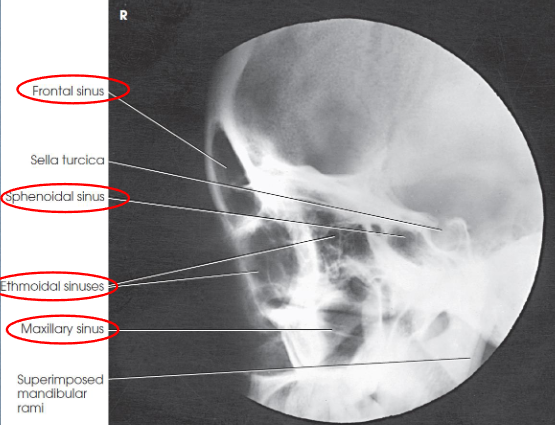

Lateral sinuses

patient position:

upright anterior oblique

can be done in dorsal decubitus position

part position:

head in true lateral

MSP parallel to IR

IPL perpendicular

extend neck so that IOML horizontal and parallel to transverse axis of IR

respiration suspended

CR:

horizontal and perpendicular

enters 1 inch posterior to outer canthus

collimation:

1 inch beyond the tip of the nose, 3 inches above the nasion, inferior to the occlusal plane, and posteriorly to the auricle

SID of 72” recommened for preoperative measurements

Lateral sinuses image criteria

demonstrates:

all four sets of sinuses

anteroposterior (AP) and superoinferior dimensions of paranasal sinuses

thickness of frontal bone

detail of side closer to IR

sphenoidal sinus best demonstrated

no rotation or tilt

sella turcica in profile

superimposed orbital roofs

superimposed mandibular rami

air-fluid levels, if present